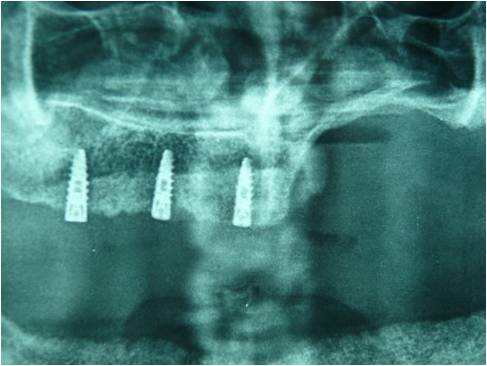

Chirurgia Oro-Mascellare per riabilitazioni protesiche post oncologiche

I pazienti che per motivi oncologici o per esito di osteonecrosi per uso di farmaci della categoria bifosfonati (in uso nelle gravi forme di osteoporosi o nel trattamento coadiuvante delle metastasi ossee)hanno subito gravi demolizioni dei mascellari e conseguente perdita della funzionalità masticatoria necessitano di ricostruzione e rifunzionalizzazione dell'apparato masticatorio con ricostruzione dell'osso mandibolare o del mascellare superiore attraverso innesti di osso , di lembi mucosi e/o muscolari di vicinanza ed a volte di implantologia preprotesica con impianti zigomatici , pterigoidei o convenzionali , tutto cio'con il fine di ripristinare una corretta funzione ma anche una auspicabile vita di relazione.

Protesi Sociale

I pazienti parzialmente o completamente edentuli presentano importanti deficit masticatori , fonatori ed estetici .

Presso le nostre sedi è possibile trattare tali casi attraverso l'installazione di protesi rimovibili che ripristinino le arcate dentarie consentendo al soggetto una corretta funzione masticatoria ed una normale vita di relazione.

Nei casi in cui il paziente abbia subìto , per motivi oncologici o chirurgici in generale , una massiva demolizione delle strutture mascellari è disponibile un servizio dedicato di terapia implantoprotesica allo scopo di ristabilire le adeguate funzioni cui il cavo orale è predisposto cercando di limitare il piu' possibile i deficit sopraggiunti.